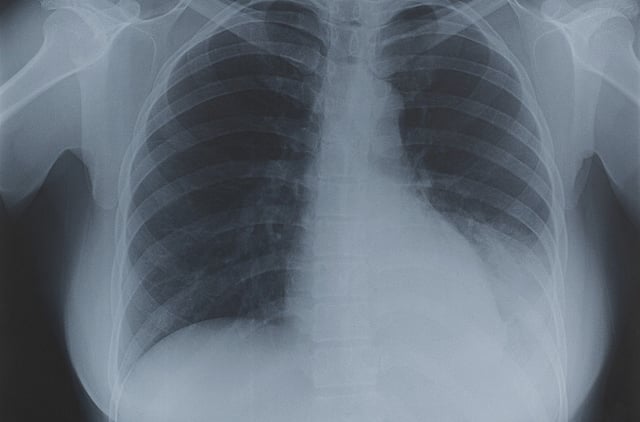

Abu Dhabi: Fitness certificates for newcomers to the UAE are stamped as unfit if a tuberculosis (TB) scar has been detected through a chest X-ray; a practice that health experts feel is outdated.

TB scars mainly arise when the outer layer of the lung has been infected in the past and not necessarily by TB. Yet according to the UAE federal law, those found to have old pulmonary TB, are considered unfit, and a lifetime ban is stamped in their passports.

UAE Ministerial decree's 28/2010 and 7/2008 indicate that all newcomers who have been found to have active or old pulmonary TB in a chest X-ray are denied a fitness certificate since they are considered "unfit" citizens."I would understand why active TB cases could pose a threat to society, since it's contagious, however when a patient is found to have a scar in a chest X-ray it doesn't necessarily mean it's due to TB. It only means the pervious infection's such as pneumonia, have produced a scar," he said.